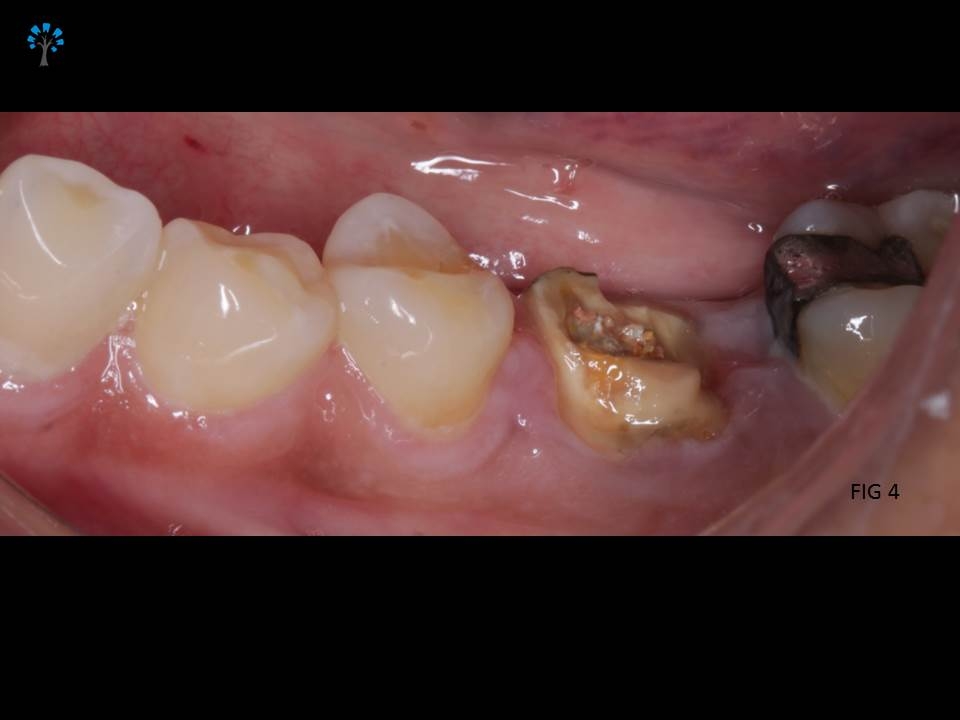

An elderly patient reported with a dislodged gold crown.

Examination revealed fracture of the distal portion of the tooth (Fig 1,4).

Given the medical status of the patient and based on certain existing favorable anatomic features with diagnosis from the Intra oral xray (Fig 2), we decided to retain the tooth and restore it.